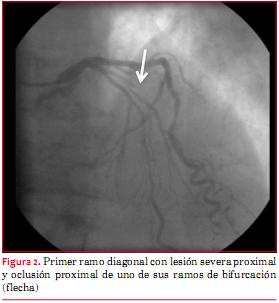

Paciente de 82 años de sexo masculino con antecedentes de tabaquismo e hipertensión arterial. Veinticuatro horas antes del ingreso presentó dolor retroesternal opresivo intenso durante un esfuerzo moderado, sin irradiaciones, acompañado de disnea, que calmó espontáneamente a los 15 minutos y por el cual no consultó. El día del ingreso reiteró nuevo episodio de dolor de iguales características pero de mayor intensidad, en reposo, acompañado de disnea y síndrome neurovegetativo, por el que consultó a las seis horas de iniciado el cuadro. Al ingreso se destacaba hipotensión arterial de 80/60 mmHg, estertores crepitantes en tercio inferior de ambos campos pulmonares y un soplo sistólico regurgitante en foco mitral de intensidad 2/6, irradiado a axila. Se realizó electrocardiograma en el que se comprobó infradesnivel del segmento ST de hasta 3 mm en DII, DIII y aVF y de V2 a V6 y supradesnivel del segmento ST de 1 mm en aVL (figura 1). Los marcadores cardíacos fueron positivos (CK total/MB 795/197 UI/l y troponina T 1,30 ng/ml). Se inició tratamiento antiisquémico con nitroglicerina i/v, persistiendo con ángor, siendo referido para cineangiocoronariografía de urgencia a las ocho horas de iniciado el segundo episodio de dolor. Esta se realizó por acceso radial derecho. Se comprobó que la arteria descendente anterior presentaba una lesión severa y extensa de tercio medio, el primer ramo diagonal una lesión severa proximal y oclusión proximal de uno de sus ramos de bifurcación, la arteria coronaria derecha una lesión moderada distal y el ramo descendente posterior una lesión crítica proximal (figuras 2 y 3). El procedimiento fue mal tolerado, con desaturación arterial de oxígeno por falla ventricular izquierda congestiva, extrasistolía ventricular frecuente e hipotensión arterial que requirió infusión de noradrenalina. Por este motivo y dado que el vaso culpable, probablemente el ramo de división ocluido del primer ramo diagonal, era un vaso de escaso desarrollo, se decidió no intentar una angioplastia coronaria. Se colocó balón de contrapulsación intraaórtico (BIAC). Por ecocardiograma (transtorácico y transesofágico) se comprobó rotura completa de músculo papilar anterior, insuficiencia mitral severa por eversión de la valva mayor de la mitral; función sistólica global conservada, sin alteraciones evidentes de la motilidad segmentaria (figura 4). El paciente evolucionó al shock cardiogénico refractario al tratamiento, falleciendo a las 12 horas de ingresado.

La rotura del músculo papilar posteromedial es ocho a diez veces más frecuente que la del músculo papilar anterolateral. Esto se debe a que la irrigación de este último es doble: desde el primer ramo diagonal de la arteria descendente anterior y del primer ramo marginal de la arteria circunfleja. Por el contrario, el músculo papilar posteromedial recibe irrigación solamente desde la arteria coronaria derecha(3).